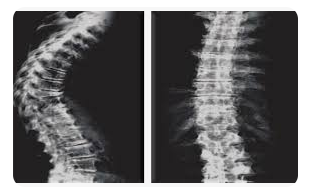

A Densitometria Óssea (DO) é uma técnica fundamental que emprega um equipamento para a leitura da densidade mineral óssea (DMO).

A principal aplicação da DO é a detecção precoce de osteoporose, doença caracterizada pela baixa massa óssea, aumento da fragilidade óssea e consequente aumento do risco de fraturas.

A densitometria óssea por raios-X de dupla energia (DXA) é considerada o padrão ouro para o diagnóstico de osteoporose pela Organização Mundial da Saúde (OMS) desde 1994.